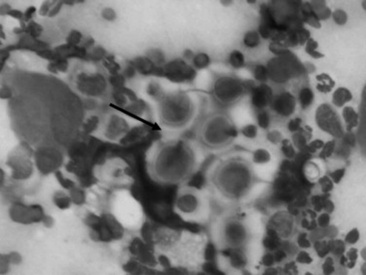

CYTOLOGY

Fungal hyphae may be identified in airway fluid or in impression smears obtained from biopsied masses. Clinicians must be careful in attributing significance to the presence of fungal elements in a TTA. Fungal hyphae are often present either free or in large mononuclear cells in tracheal aspirates from healthy horses.90 A study of healthy thoroughbred racehorses showed that 70% had fungal elements detected in their tracheal aspirates.92 None of the horses from either study had other evidence of fungal pneumonia. Barn fungus such as Alternaria species are nonpathogenic and rarely incite an inflammatory response in the host. The organisms often have a blocklike appearance and may be colored (Fig. 31-18, A and B). A normal predominance of macrophages, lymphocytes, and nondegenerate neutrophils (<5% to 10%) would be expected.

image image

Fig. 31-18 Alternaria species from transtracheal wash specimens obtained from healthy horses. A, An extracellular spore (arrow) with several macrophages, squamous cell (indicative of pharyngeal contamination. B, Intracellular spores (arrow) within binucleated macrophage.

Courtesy Elizabeth Welles, Auburn University, Ala.

To be significant cytologically, large numbers of fungi should be involved in the inflammatory process within the lung. With fungal pneumonia, aspirates may contain predominately neutrophils that often are degenerate and may contain intracellular fungal hyphae. If processing of the sample is delayed, extracellular fungi may be phagocytized, which confuses the interpretation. Some fungi have characteristic morphologic features that can permit an early presumptive identification (Table 31-5).